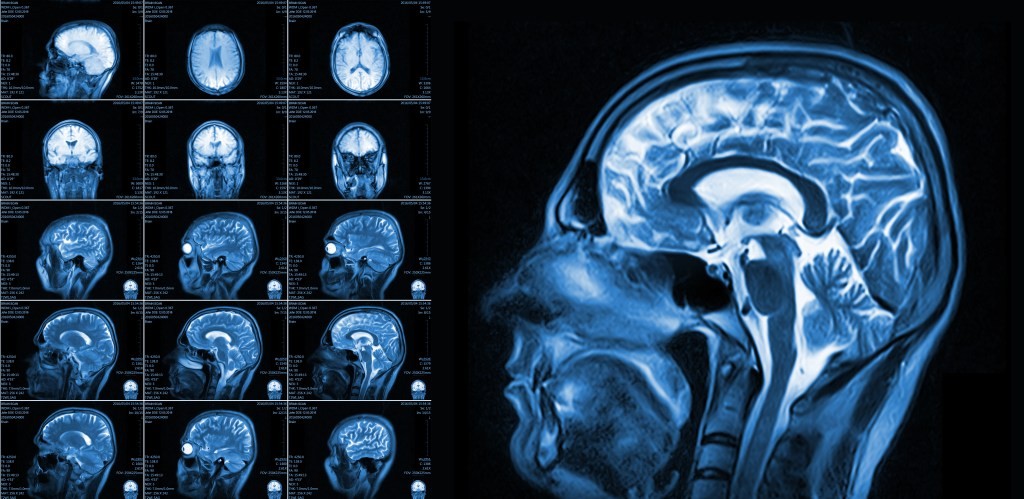

Alla fine dello studio, i benefici sul flusso sanguigno cerebrale erano chiari. Le prove di imaging hanno mostrato un significativo miglioramento della brain vascular responsiveness, ossia la capacità dei vasi sanguigni di dilatarsi e contrarsi per regolare il flusso sanguigno. Dopo 16 settimane di consumo di arachidi, il flusso cerebrale globale è aumentato del 3,6% rispetto al periodo di controllo. “CBF is an important physiological marker of brain vascular function and refers to the amount of blood that flows through the brain, delivering oxygen and nutrients that are essential for maintaining brain health,” Dr. Peter Joris, the study’s author, said in a statement. Una bassa CBF è associata al decadimento cognitivo e può influire su funzioni come l’attenzione, la velocità psicomotoria e la memoria. Quando Joris e i suoi colleghi hanno esaminato la materia grigia del cervello, sede dei corpi cellulari dei neuroni, hanno trovato che il flusso sanguigno era aumentato del 4,5%. I lobi frontali hanno registrato un incremento del 6,6%, mentre i lobi temporali sono saliti del 4,9%. Queste regioni svolgono ruoli chiave in memoria, linguaggio, decisioni e controllo emotivo. Questi benefici vascolari si sono tradotti in un miglior ricordo. Durante un test di memoria, le persone che hanno mangiato le arachidi hanno riconosciuto più parole da una lista che avevano visto 20 minuti prima rispetto al periodo di controllo. “For the first time, we demonstrated that peanut intake improved brain vascular function in healthy older adults,” Joris said.